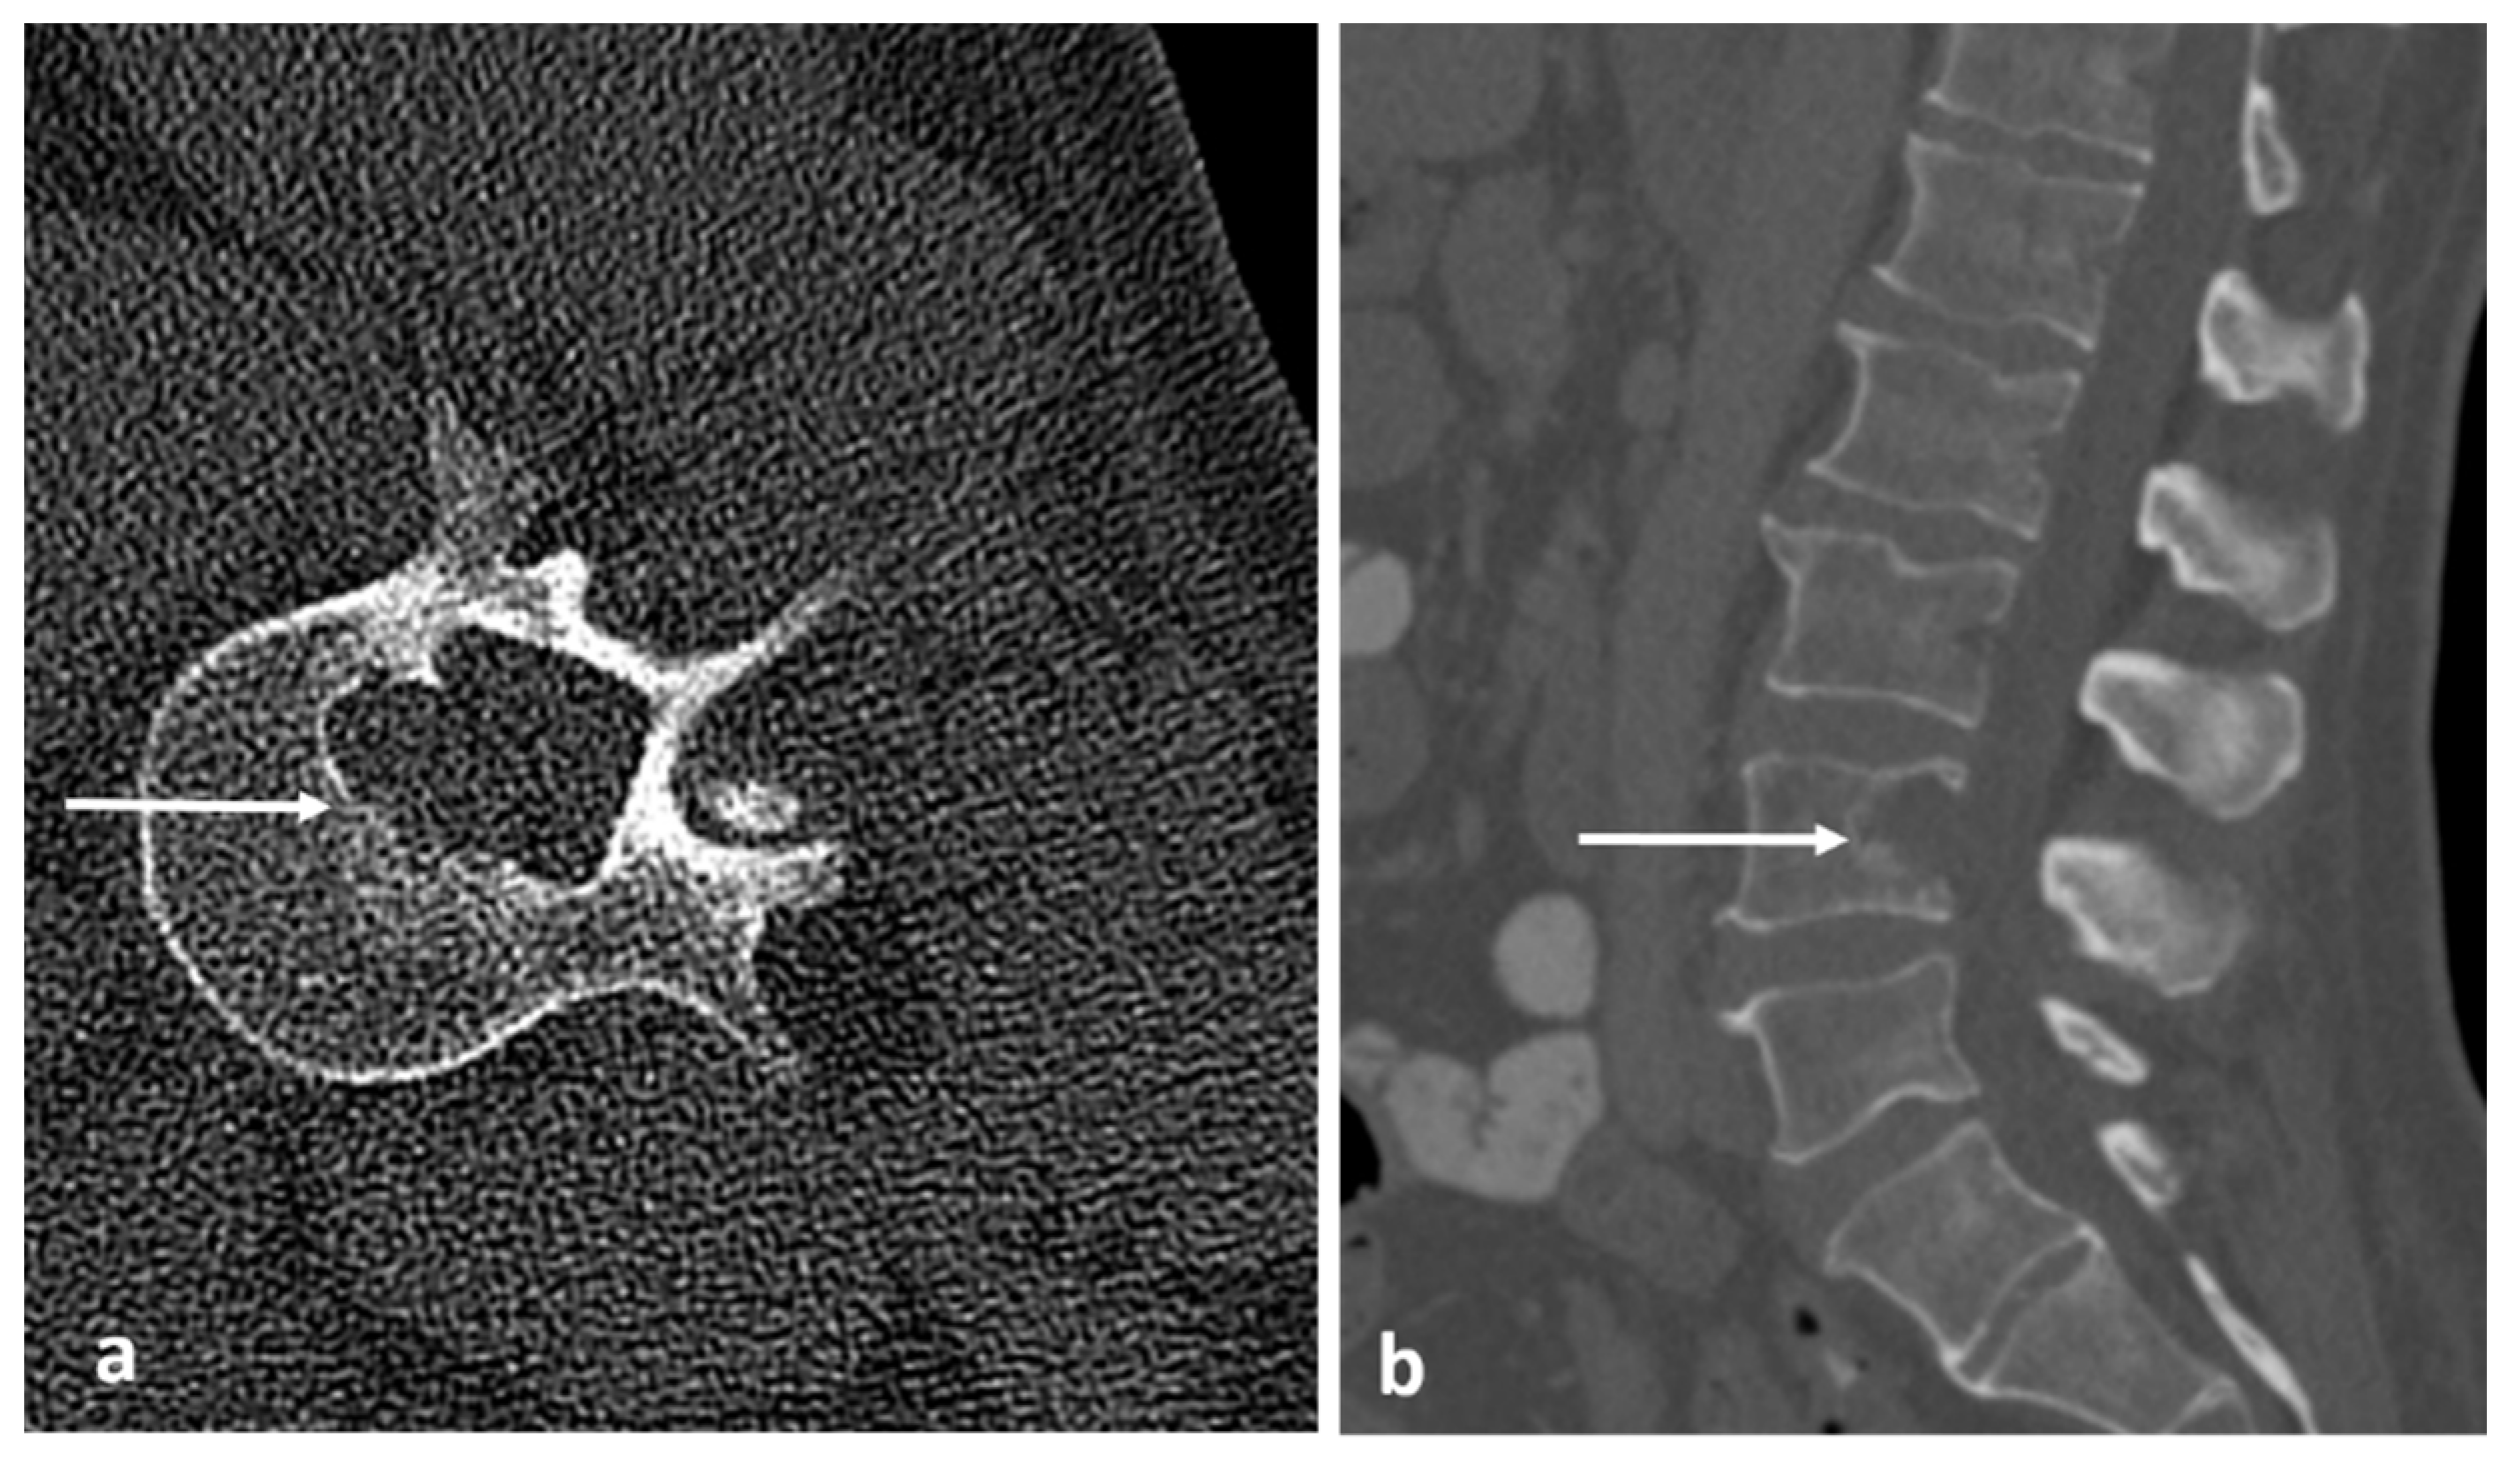

| Benign notochordal tumour | Midline lesion in the body. Sclerosis or trabecular thickening typically, but lysis can be present. | Low T1 and high T2 signal. No enhancement. |